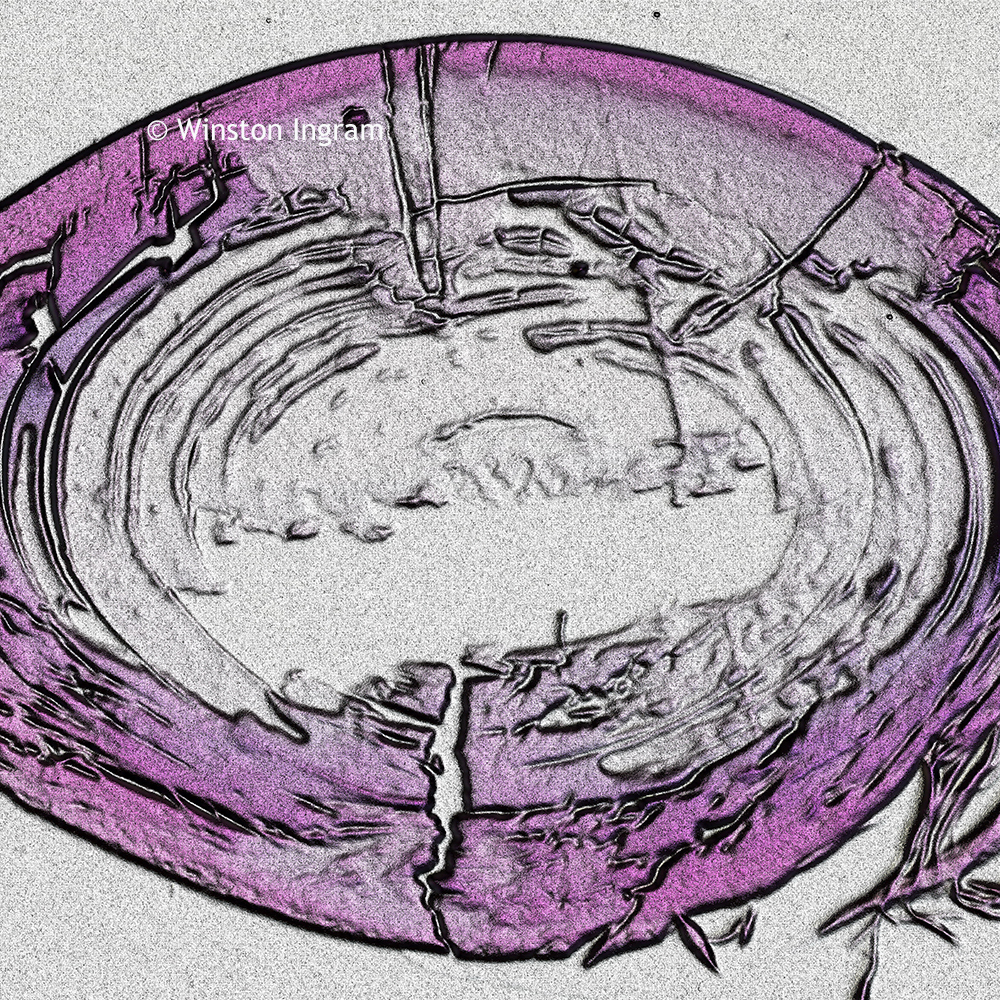

Professor Winston Ingram has worked as a scientist, photographer, artist and musician for over fifty years. He is currently retired and resides in London. These images are from his opthalmalic and dental microscopy collection of art work. He used a microscope to capture images of the eyes and teeth.